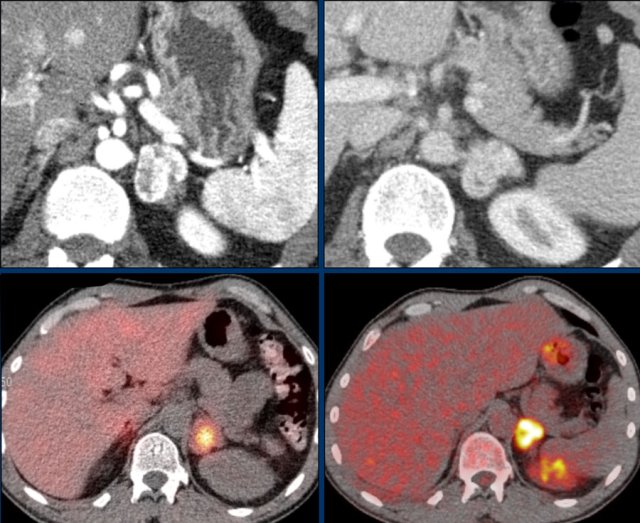

The axial venous phase CT on the left shows a large inhomogeneously enhancing right adrenal lesion with a small cyst, which could not be diagnosed as an adenoma with CT washout, making it an indeterminate lesion.

The plasma free metanephrines were elevated and the lesion was diagnosed as a pheochromocytoma.

MIBG SPECT for staging showed intense uptake in only the right adrenal gland.

PET-CT was also performed, which in contrast showed uptake only slightly higher than normal liver.

This is highly unusual for pheochromocytomas, which are usually very FDG-avid, even when they are benign.

If the primary tumor lacks FDG uptake, the sensitivity for finding metastases on an FDG PET-CT will be very low.